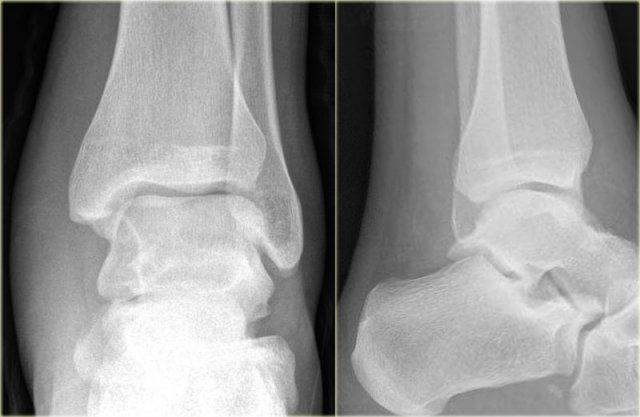

Here we have images of an extremely difficult case.

This woman had a distortion of the ankle and had pain on both medial and lateral side.

She was referred to the radiology department by her general practitioner.

The technician made the standard AP-, Mortise- and lateral view and showed them to the radiologist, who was a little bit puzzled.

First study the images and then continue reading.

The findings are:

• Soft tissue swelling both medial and lateral (red arrows).

Especially the medial swelling should make you consider a pronation exorotation injury (Weber C).

• Lucent line on Mortise view (black arrow) and lateral view. This should make you consider a tertius fracture.

The radiologist decided first to order a CT to find out if there really was a tertius fracture.

Continue with the CT and be amazed.